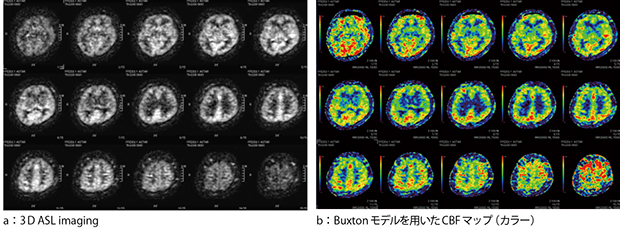

ASL imagingをモデル化する場合は,トレーサ量の流入出だけでなく,組織のT1緩和の影響を考慮する必要がある。そのため,ボクセル内を血液と組織成分を含めて均一とみなしたsingle-compartmentモデルではなく,より実際に近い two-compartmentモデルが使用される場合もある。しかし,測定や仮定するパラメータが多いことや,組織ごとのT1値をボクセルごとに測定することは困難であり,臨床応用としては現実的ではない。そこで,Buxtonらは,組織ごとのT1値の代わりに近似的に血液のT1値を用いても誤差はほとんどないことを示しており2),現在多く用いられている。当社でも,Buxtonモデルを用いたASLのモデル化による定量化が可能であり,コンソール上で簡便に計算することができる(図2)。

図2 Buxtonモデルを用いたASLの定量化